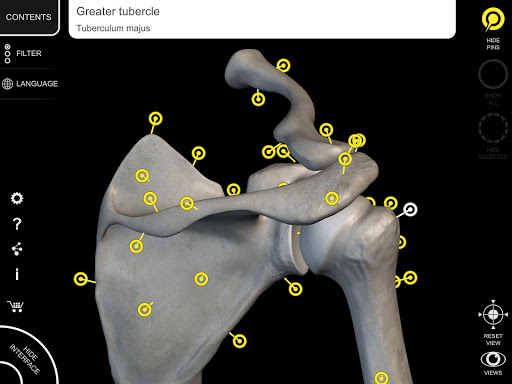

Each bone of the human skeleton has been reconstructed in 3D, you can rotate and zoom in on each model and observe it in detail from any angle.

By selecting models or pins you will be shown the terms related to any specific anatomical part, you can select from 12 languages and show the terms in two languages simultaneously.

• Interactive Pin allow visualization of the term relative to every anatomical detail